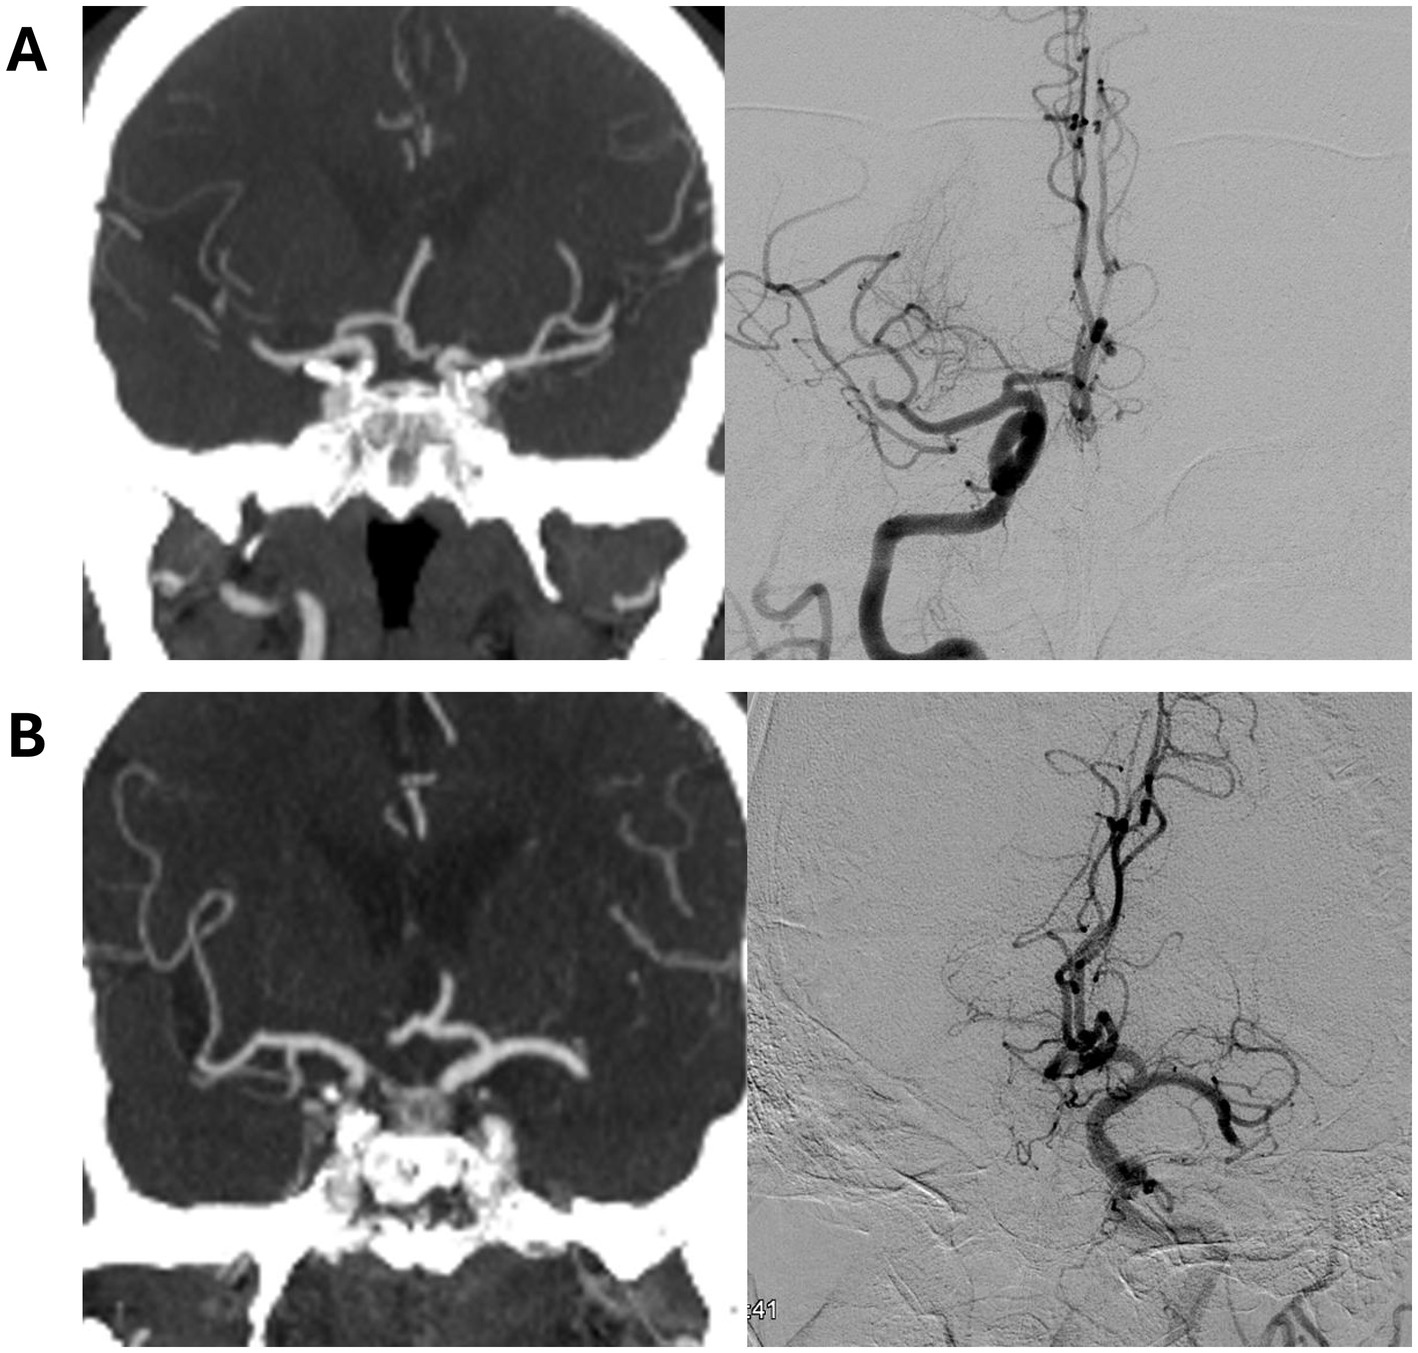

Figure 1

Definition of thrombus migration by discrepancy between CT angiography and digital subtraction angiography. Representative examples show (A) intersegmental thrombus migration from the right MCA M1 segment to the M2 segment and (B) intrasegmental thrombus migration in the left MCA.